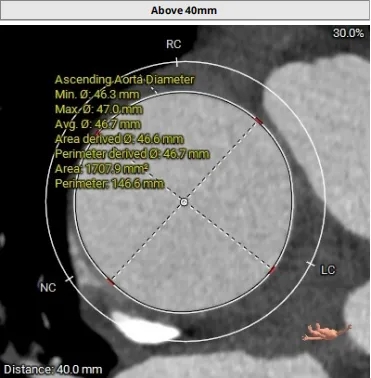

升主动脉扩张AAO 47mm

周长147.2 周长径46.9

周长146.5 周长径46.7

STJ及升主可见明显扩